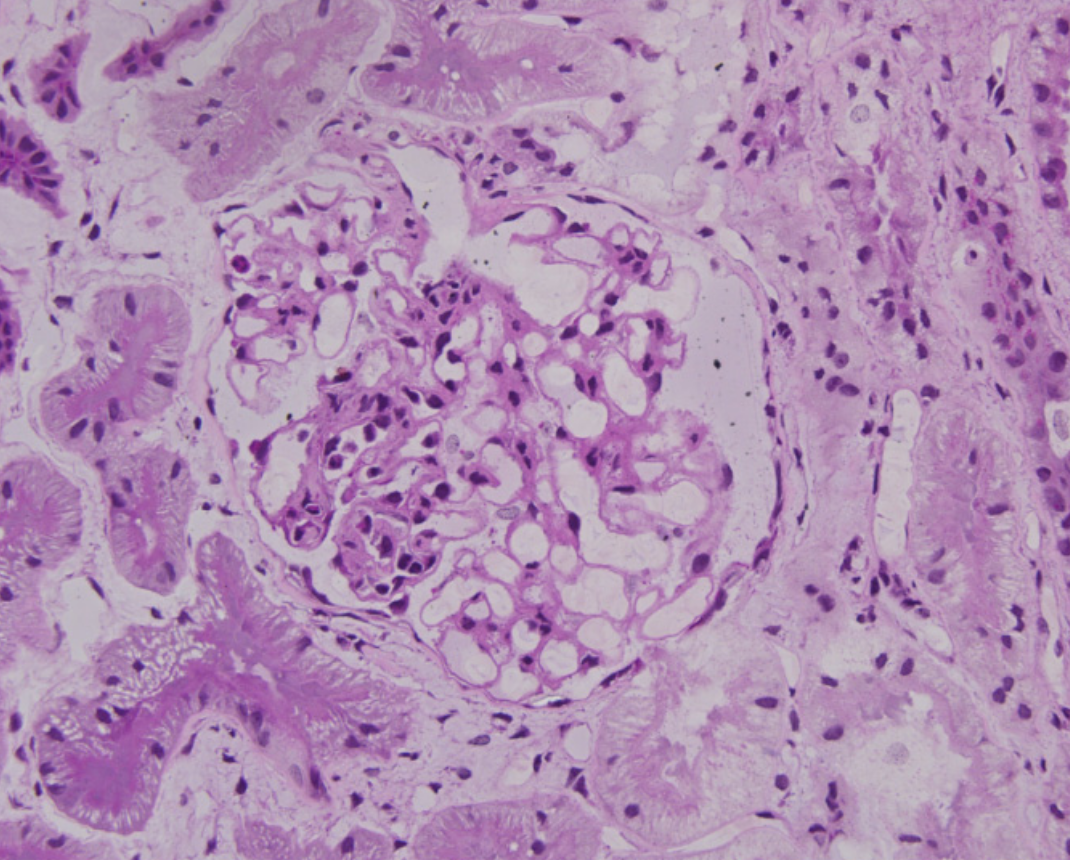

Sclérose glomérulaire segmentaire

Compter toute adhésion sans nécessité de sclérose. Ne pas compter une sclérose globale.